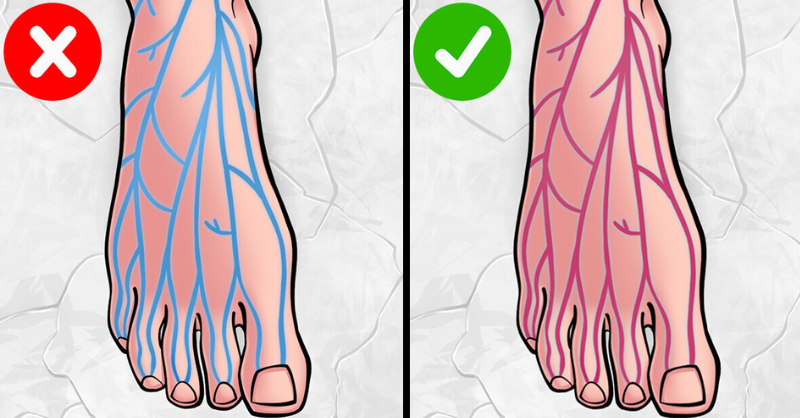

Leg Veins Turning Purple? Here’s What You Need to Know

Purple veins on the legs are a common occurrence, especially among older adults and those whose jobs require prolonged sitting or standing. In the beginning, these veins may...